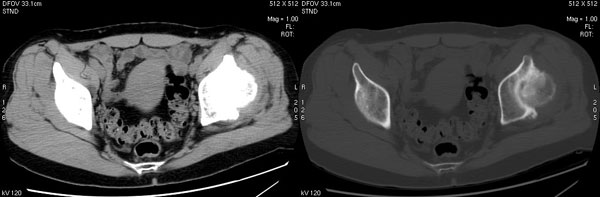

以下是引用jiajie在2006-7-14 17:19:00的发言:[br]ct所见:双侧髋关节不对称,左侧关节间隙变窄,关节面毛糙。左侧股骨头变形、无明显变小,前上缘与髋臼融合,融合处骨质明显增生硬化,并见数个小囊变影。股骨头下端与股骨颈交界部见囊样变,邻近肌肉内见囊样密度减低区,ct值24hu。右侧髋关节形态未见异常。[br][br]ct诊断:左侧髋关节结核可能,请结合临床资料进一步分析。

以下是引用lihuuuu在2006-12-5 10:14:00的发言:[br]定位像示:左侧髋臼变浅,倾斜度加大,髋臼外上缘呈波浪状不规则,骨质增生硬化,髋关节上缘间隙明显变窄,股骨头向外上轻度移位。轴位像示:左侧股骨头变形,前上缘与髋臼融合,融合处骨质明显增生硬化,并见数个小囊变影。股骨头下端与股骨颈交界部见囊样变,邻近肌肉内见密度减低区,ct值24hu,内缘见弧形高密度钙化影。右侧髋关节形态未见异常。[br]ct诊断:左侧髋臼发育不良[br] 左侧股骨头缺血性坏死[br] 左侧肌肉内低密度影伴有高密度钙化-考虑早期骨化性肌炎[br] [br]“我认为在描述上已经写了肌肉部分,印象诊断里应该写主见”[br]